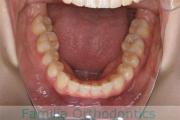

No.22V-409

- 叢生

- 16歳

- 女性

- 抜歯部位

- 上:

- 44

- 下:

- 8|58

- 主な使用装置:

- FEA

- 治療にかかった費用:

- 86万円

八重歯を治したいということで来院されました。下あごの左ずれのある上顎前突(出っ歯)・叢生(でこぼこ)でしたので、上は左右から、下はで左のみ小臼歯を抜歯して、歯科矯正用アンカースクリューとマルチブラケット法にて治療を行いました。2年強、30回程度の通院が必要でした。

上下とも前歯の叢生(でこぼこ、凹凸、ガタガタ)があるため、保定を怠ると後戻りのリスクがあります。